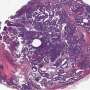

Know someone who’s been diagnosed with breast cancer? There’s a good chance that person has received hormone therapy. Estrogen receptor-positive (ER+) breast cancers account for about 75% of cases. Hormone therapy is one of the most common and effective treatments. However, it’s far from a cure.